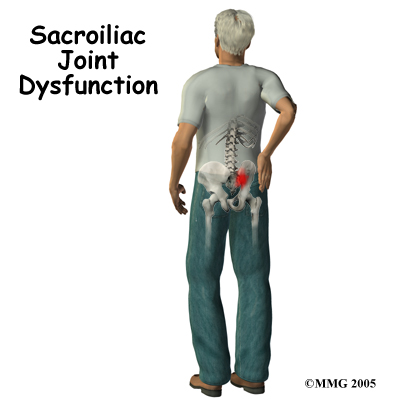

A painful sacroiliac joint is one of the more common causes of mechanical low back pain. Sacroiliac (SI) joint dysfunction is a term that is used to describe the condition - because it is still unclear why this joint becomes painful and leads to low back pain. Sacroiliac joint dysfunction can be a nuisance but it is seldom dangerous and rarely leads to the need for surgery. Most people who suffer from this problem can reduce the pain and manage the problem with simple methods.

At the lower end of the spine, just below the lumbar spine lies the sacrum. The sacrum is a triangular shaped bone that is actually formed by the fusion of several vertebrae during development. The sacroiliac (SI) joint sits between the sacrum and the iliac bone (thus the name “sacroiliac” joint). You can see these joints from the outside as two small dimples on each side of the lower back at the belt line.

The most common symptoms from SI joint dysfunction are low back and buttock pain. The pain may affect one side or both SI joints. The pain can radiate down the leg all the way to the foot and may be confused with a herniated disc in the lumbar spine. The pain may radiate into the groin area. People often feel muscle spasm in one or both of their buttocks muscles.